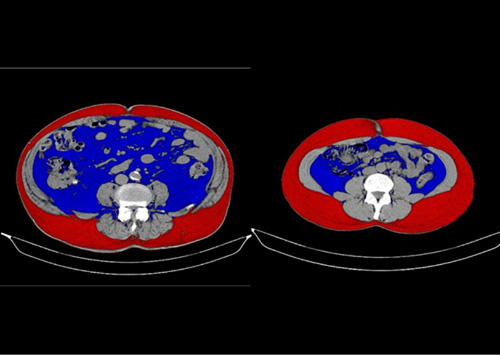

全身CT 全身CT

全身CT(オプション検査、内臓脂肪測定つき)

1回の検査で肺がん、肝腫瘍、膵がん、腎がん、胆石症や尿路結石、その他腹部腫瘍のチェックが可能です。

さらにCT画像をコンピューターで解析することで、国際的な標準指標であるBMIでは評価しにくい内臓脂肪量を客観的に測定できます。

内臓脂肪型肥満があると高血圧や糖尿病、脂質代謝異常、脳卒中、心筋梗塞、大動脈解離、大動脈瘤など、重篤な疾患を発症する確率が高くなります。

随時受付 / 自由診療

検査費用:¥18,700(税込)

内脂肪測定のみ:検査費用:¥3,300(税込)